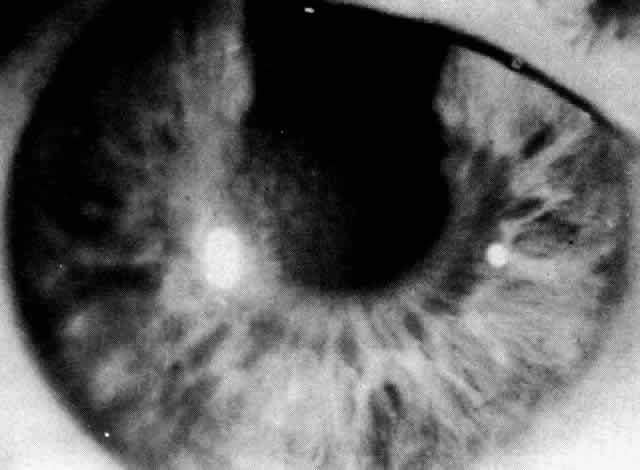

Patients with Fuchs' dystrophy rarely present with symptoms until after 50 years of age. Patients progress through three phases. In phase one, patients are asymptomatic and simply have guttata (Fig. 11) and pigment dusting of the endothelium. Patients who progress to phase two present with complaints of hazy vision and glare as stromal and epithelial edema develop. Epithelial edema progresses to bullae that may rupture and may cause severe pain. In phase three, subepithelial connective tissue develops and edema decreases. Patients become more comfortable but have a significant decrease in vision.

Fig. 11. Fuchs' dystrophy: beaten metal appearance of endothelium.